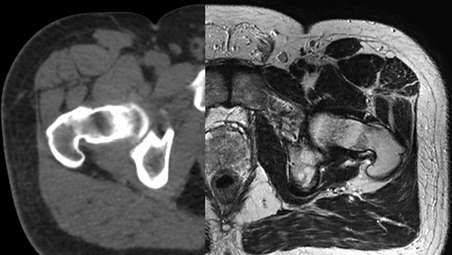

The Ingenia MR-RT XD platform’s MR-only radiotherapy capability turns your MR into an authentic single modality simulator. With innovative MRCAT (MR for Calculating ATtenuation), you can obtain CT-like density information for dose calculations and position verification based on a single MR scan. So you can eliminate cumbersome and error-prone CT-MR registration, and make MR-based workflows more cost-efficient. - Coil solutions for RT imaging

Our innovative MRCAT (MR for Calculating ATtenuation) clinical applications lets you plan radiation therapy using MRI as primary imaging modality. Within just one, fast MR exam, MRCAT provides both excellent soft-tissue contrast for target and OAR delineation and CT-like density information for dose calculations. This not only extends the benefits of MRI’s excellent soft-tissue contrast to radiotherapy planning, but it also eliminates arduous, error-prone CT-MRI registration from the process, reducing uncertainties and complexity.

As a plug-in clinical application to Ingenia MR-RT, MRCAT Prostate + Auto-Contouring provides attenuation maps and automated, MR-based contours of prostate and organs at risk in as little as 20 minutes – all in a repeatable ‘one-click’ workflow.

MRCAT Pelvis lets you plan radiation therapy using MRI as a single modality solution. Within just one MR exam, MRCAT Pelvis provides excellent soft-tissue contrast for target and OAR delineation, and continuous Hounsfield units for dose calculations. MRCAT (MR for Calculating ATtenuation) data can be used for export to treatment planning systems for CT-equivalent** dose calculations. In addition, MR-based imaging enables CBCT-based positioning based on soft-tissue contrast with the look and feel of CT.